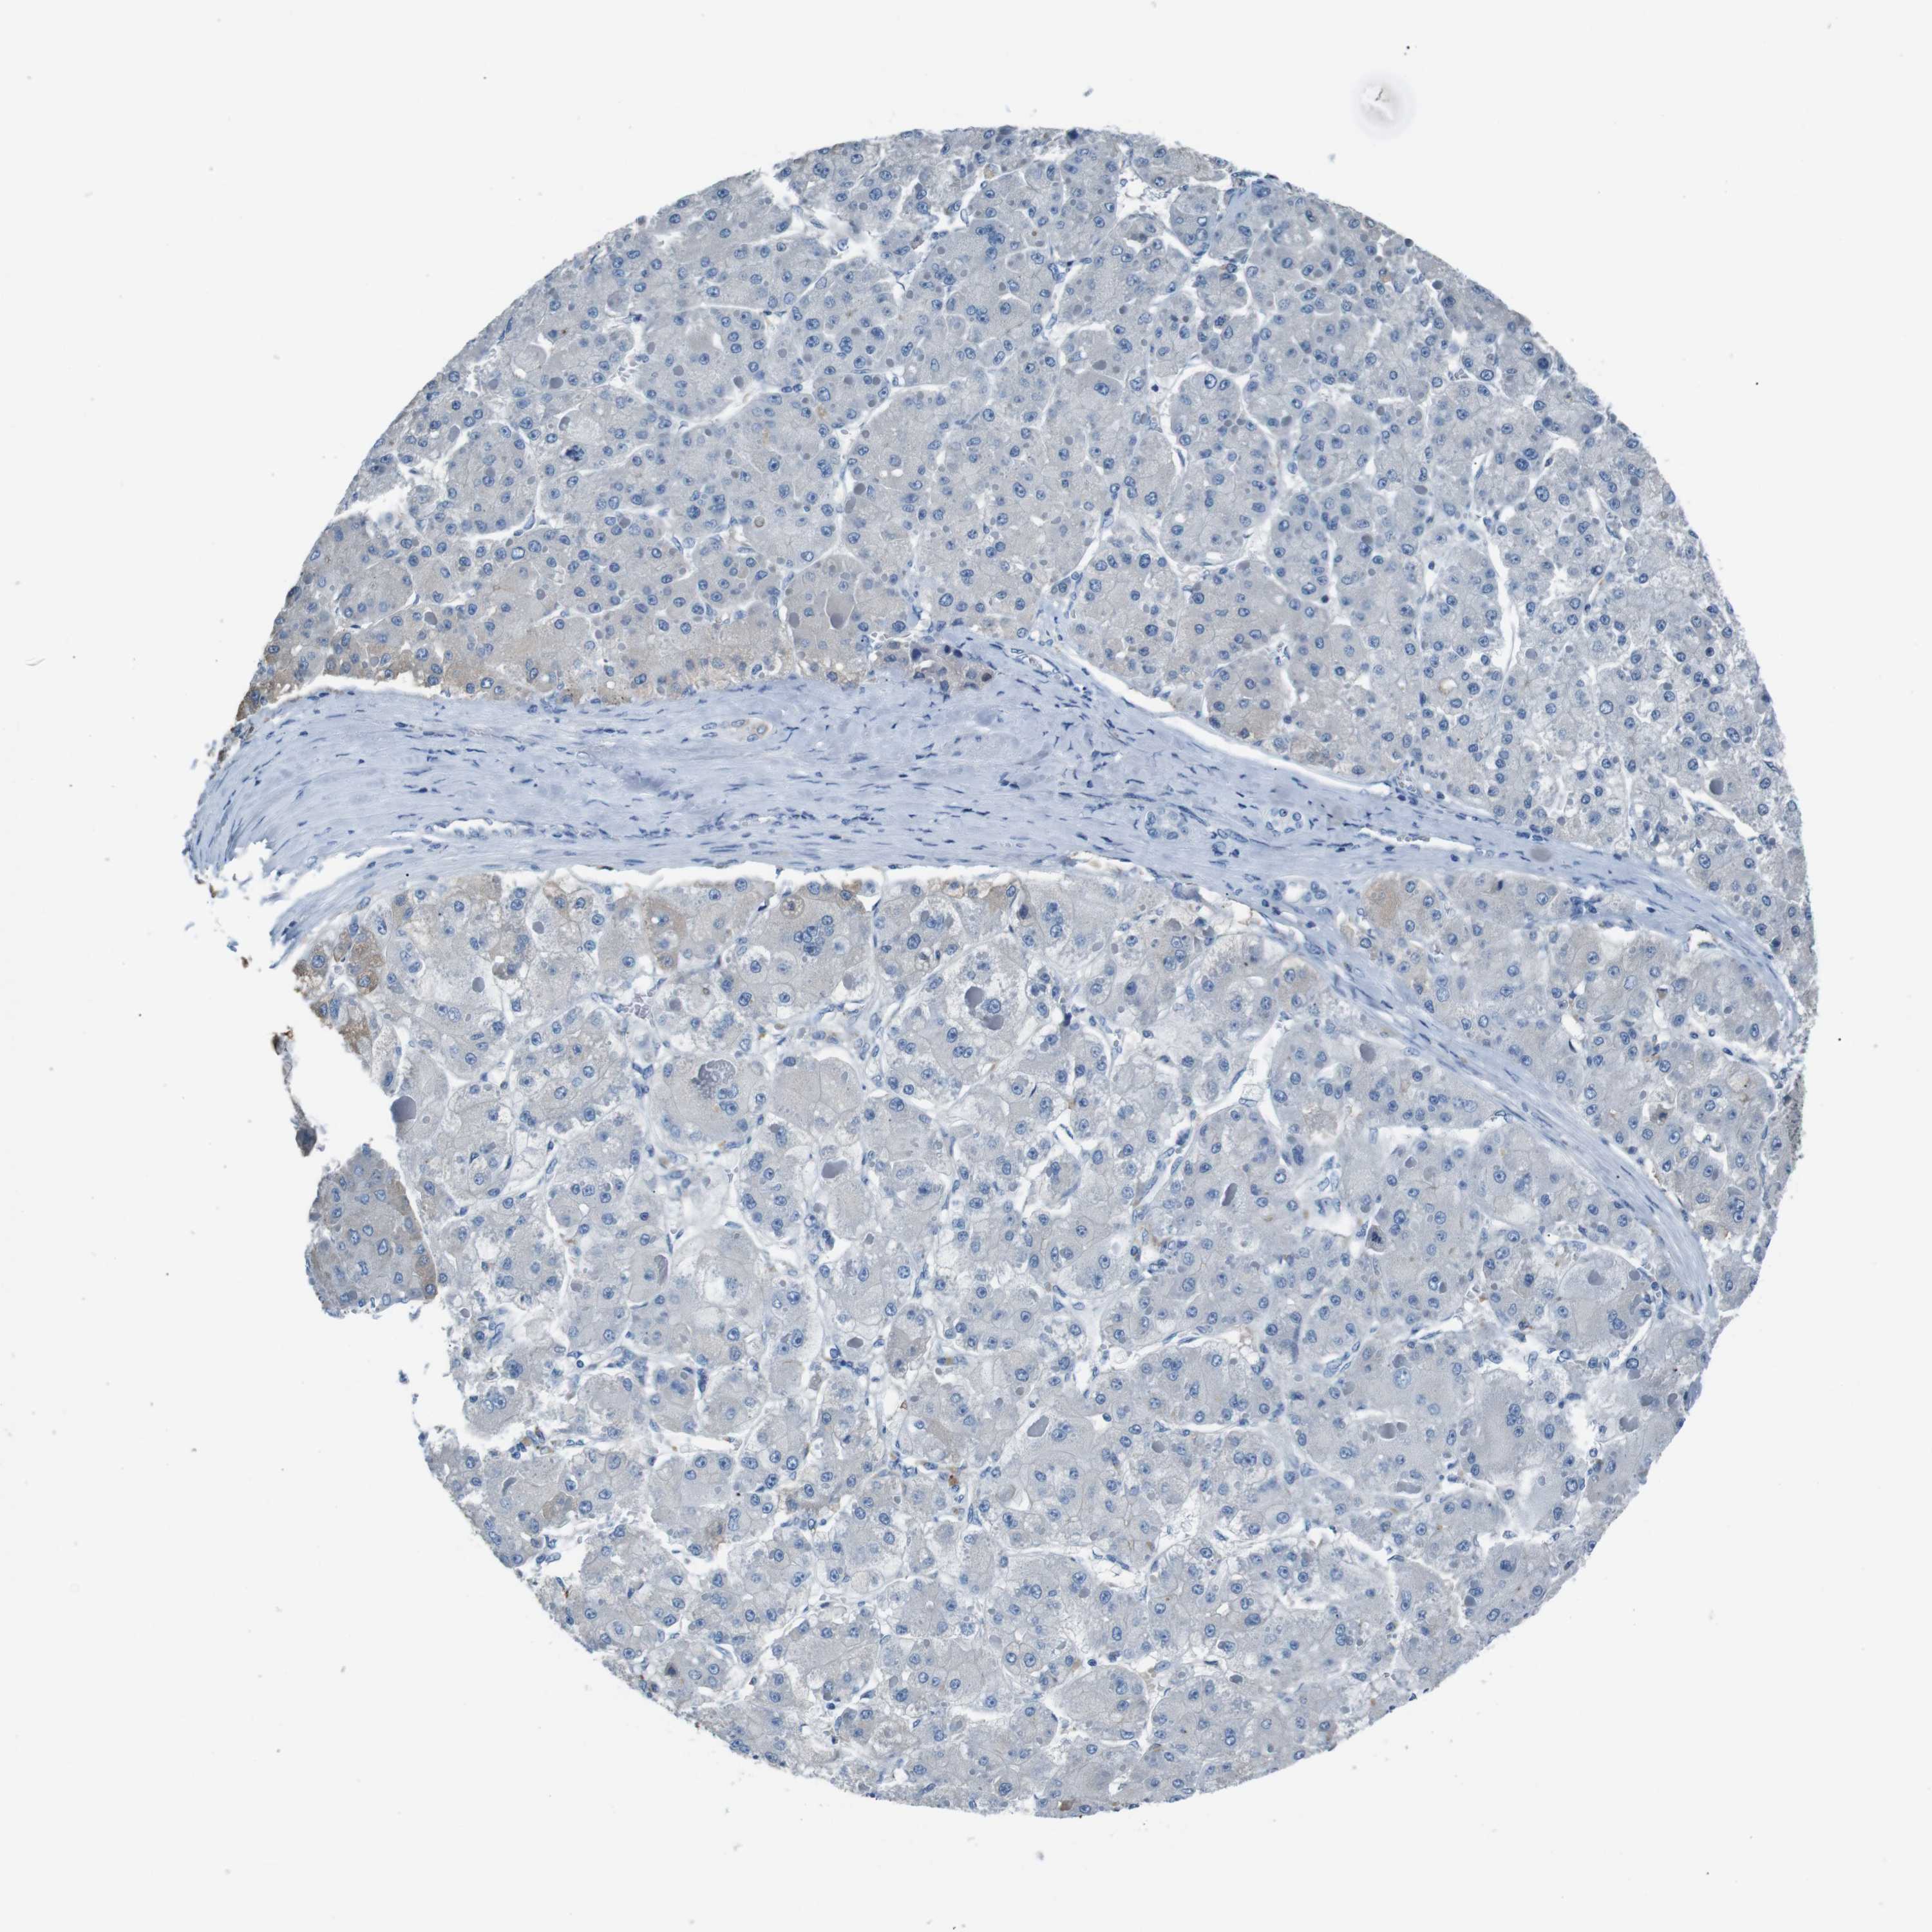

LIVER CANCER - Protein expressioni

A mouse-over function shows sample information and annotation data. Click on an image to view it in a full screen mode. Samples can be filtered based on level of antibody staining by selecting one or several of the following categories: high, medium, low and not detected. The assay and annotation is described here.

Note that samples used for immunohistochemistry by the Human Protein Atlas do not correspond to samples in the TCGA dataset.

Antibody stainingi

Antibody staining in the annotated cell types in the current human tissue is reported as not detected, low, medium, or high, based on conventional immunohistochemistry profiling in selected tissues. This score is based on the combination of the staining intensity and fraction of stained cells.

Each image is clickable and will lead to virtual microscopy that enables deeper exploration of all samples and also displays staining intensity scores, fraction scores and subcellular localization as well as patient and tissue information for each sample.

Antibody CAB010490

Staining

High

Medium

Low

Not detected

Intensity

Strong

Moderate

Weak

Negative

Quantity

>75%

75%-25%

<25%

None

Location

Nuclear

Cytoplasmic/membranous

Cytoplasmic/membranous,nuclear

Cholangiocarcinoma

Carcinoma, Hepatocellular, NOS